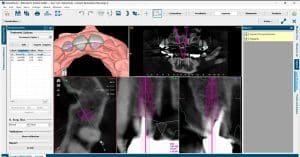

| COMPLETO (Panorámica, lateral, fotos y escaneo dental 3D) cefalometria 2D | $1,300 |

| 3D (Panorámica, lateral, fotos y escaneo dental 3D) Cefalometria 2D + Tomografía 12*10 | $2,700 |